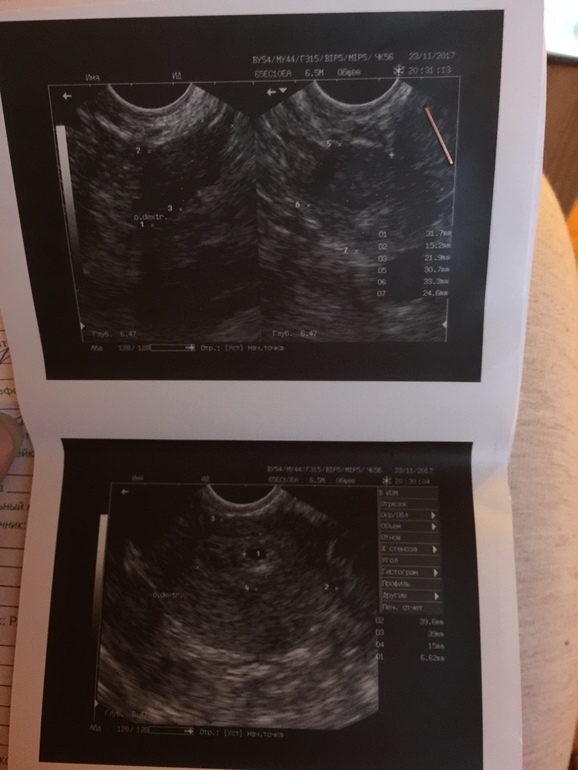

Всем привет, девочки, помогите или расскажите свои похожие истории, в общем дело в том что 4 дня назад делала УЗИ и там был пя 7 мм, без эмбриона и желточного мешочка, в итоге пошла сегодня жк и знакомая медсестра напугала что при таком размере пя эмбрион уже должен быть, в итоге поехала в другую клинику, сделала УЗИ, и пя 16 мм! За 4 каких то дня, но нашли желточный мешочек, и врач сказала что раз он появился значит беременность развивается, объяснила стадиями, сначала появляется пя, потом желточных мешок и только потом эмбрион, типа раз 2 стадия у тебя уже пошла то через недельку и эмбриона найдём. В общем 5 месяцев назад была зб и делали чистку, теперь всего боюсь как огня, уже час лежу плачу:(

это УЗИ 4 дня назад, а вот сегодняшнее